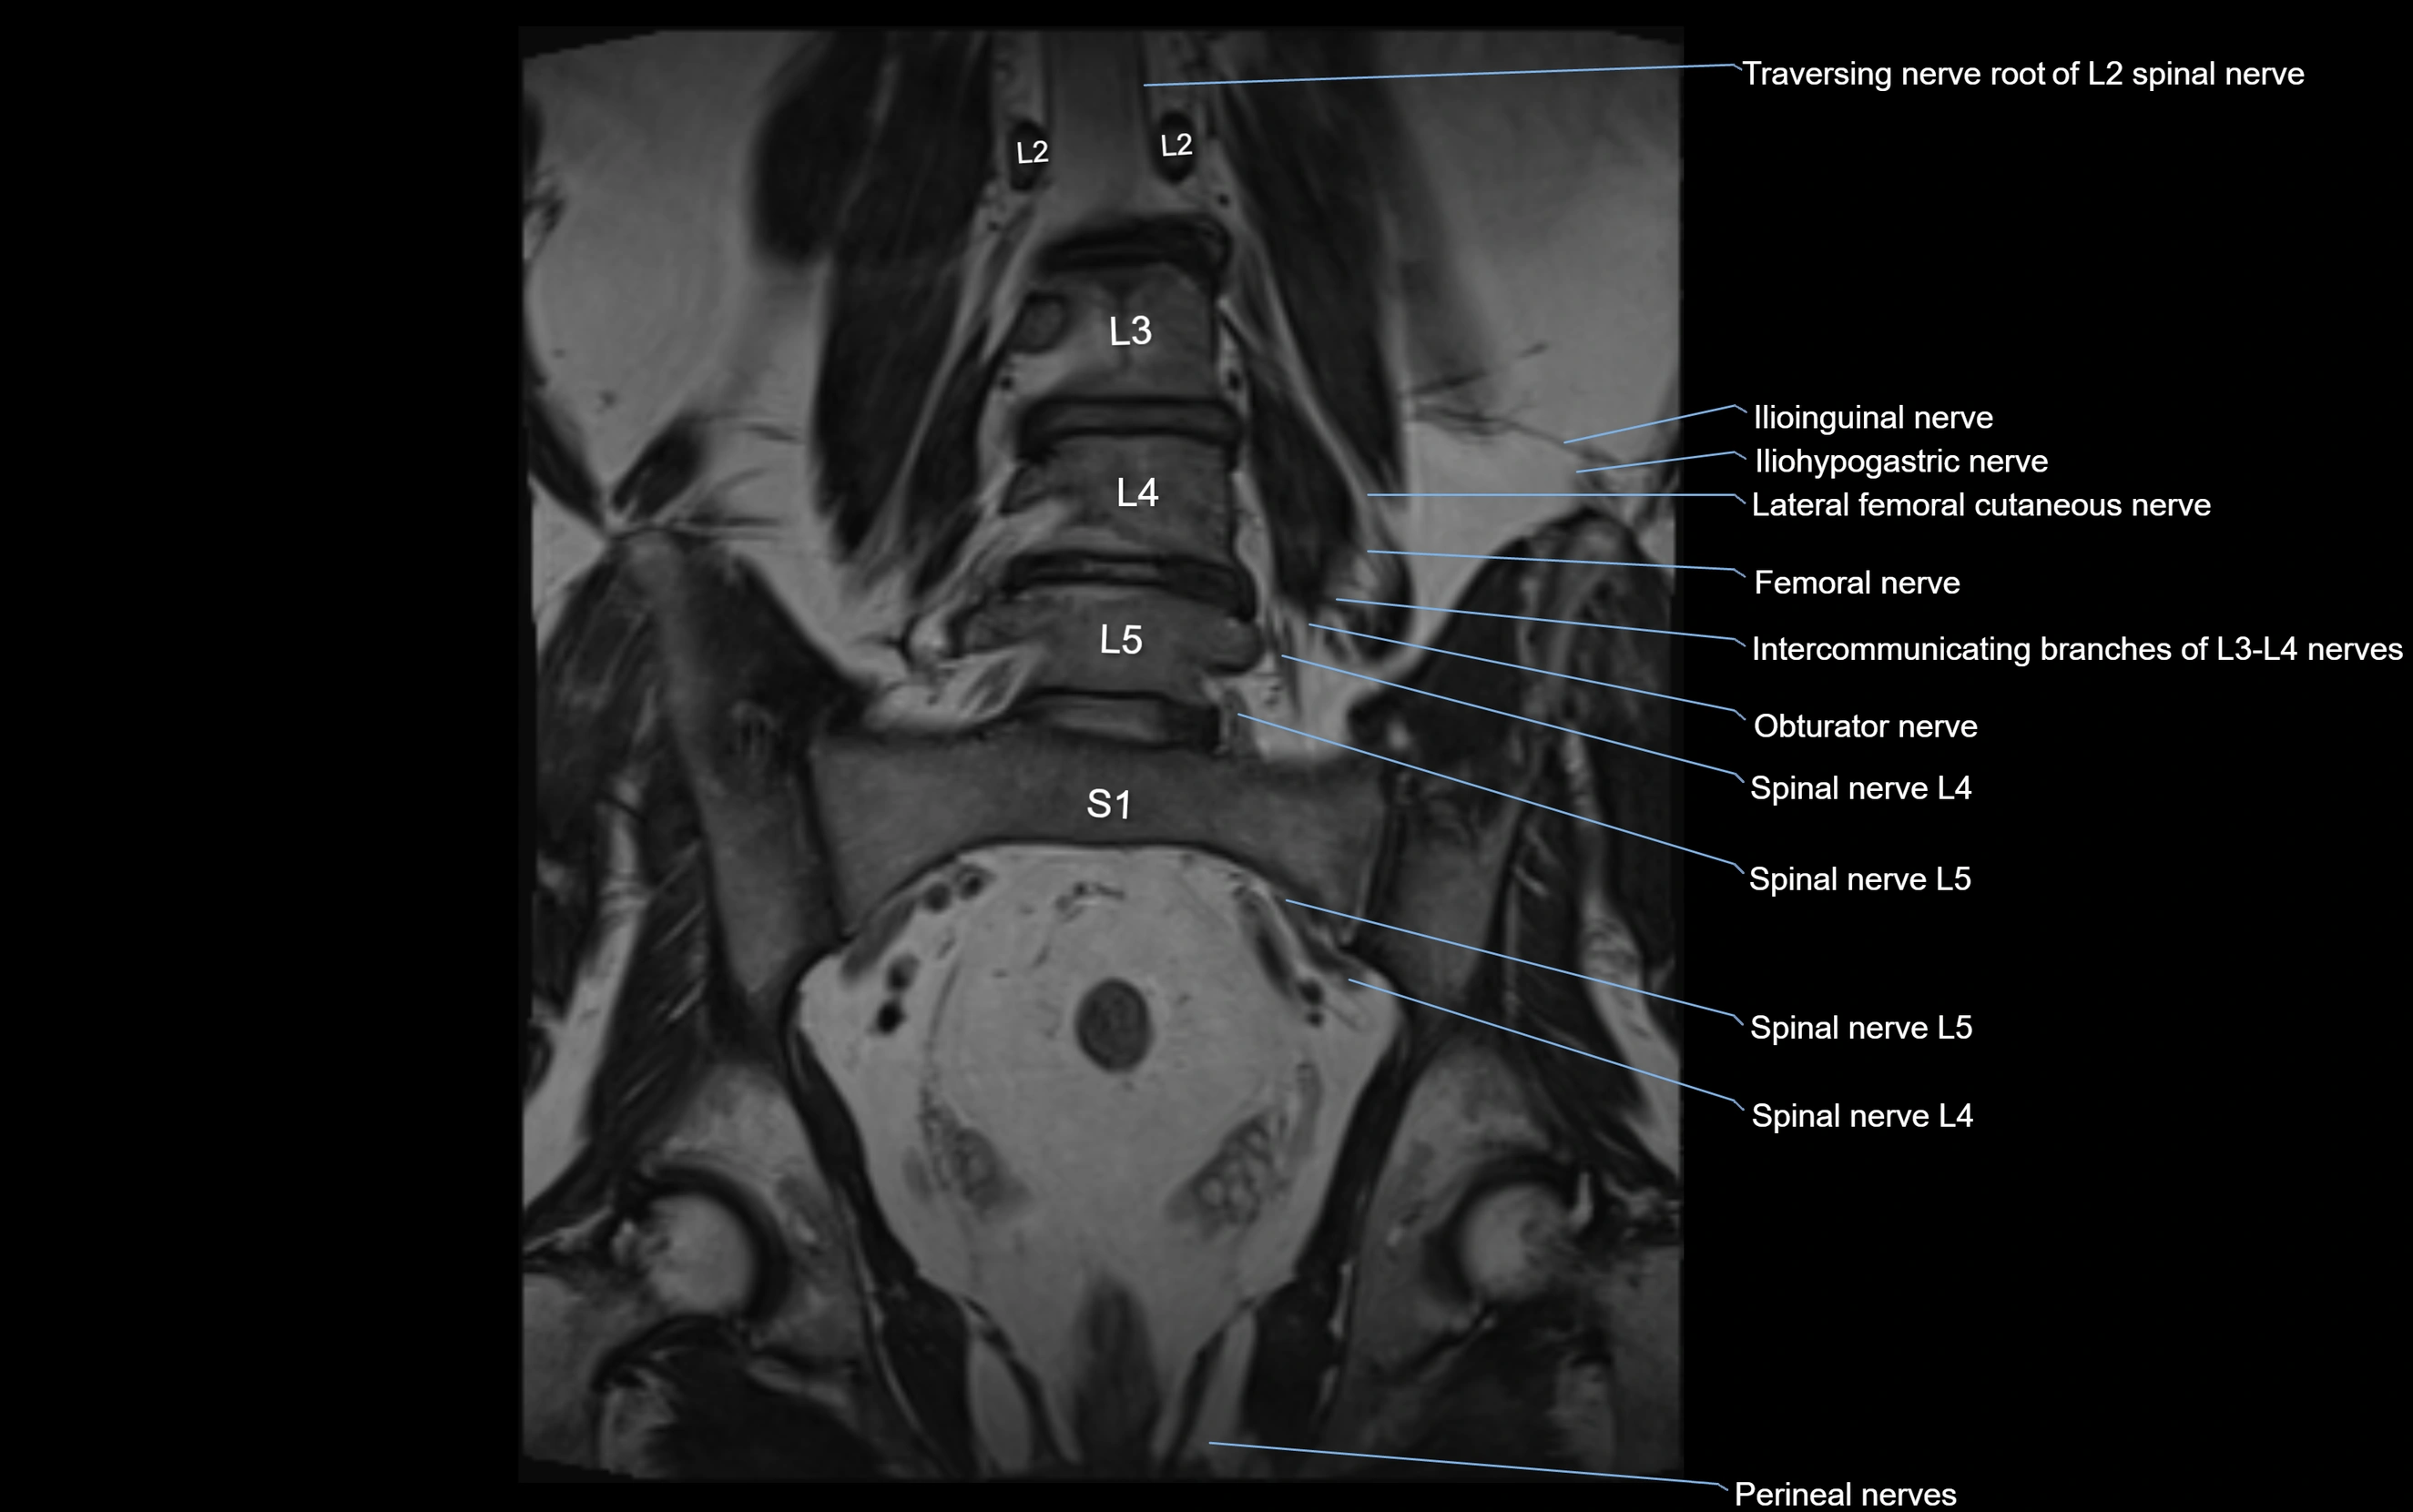

MRI Appearance

T1-weighted images:

• Nerve appears as a very thin low-to-intermediate signal intensity structure

• Surrounded by bright fat, aiding visualization

T2-weighted images:

• Nerve shows intermediate to mildly hyperintense signal compared to muscle

• Pathological involvement appears brighter

STIR (Short Tau Inversion Recovery):

• Normal nerve appears dark

• Inflamed or entrapped nerve appears bright hyperintense

T1 Fat-Sat Post-Contrast:

• Normal nerve enhances minimally

• Pathologic nerve (neuritis, entrapment, tumor infiltration) shows focal or diffuse enhancement

3D T2 SPACE / CISS:

• Nerve appears intermediate to mildly hyperintense compared to muscle

• Surrounded by bright fat or CSF, improving visualization

• Best sequence for mapping small pelvic nerves such as the anococcygeal